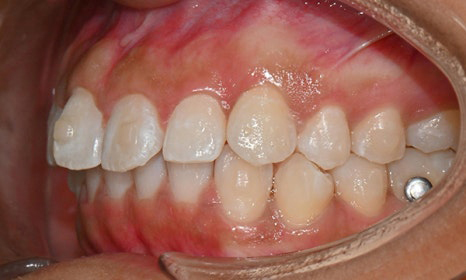

교정 마무리 후 사진 (2025.8)

최종적으로 교정을 마무리한 후에는

위아래 치아 배열이 훨씬 가지런해졌고,

깊게 물렸던 과개교합도 크게 개선되었어요.

왼쪽 작은 어금니는 목표에서 제외했던 만큼,

아직 완벽하게 교합이 맞지는 않았지만,

치료 자료를 전달해 드리고 추후 본국으로 돌아가서

남은 치료를 이어서 받기로 하셨답니다.